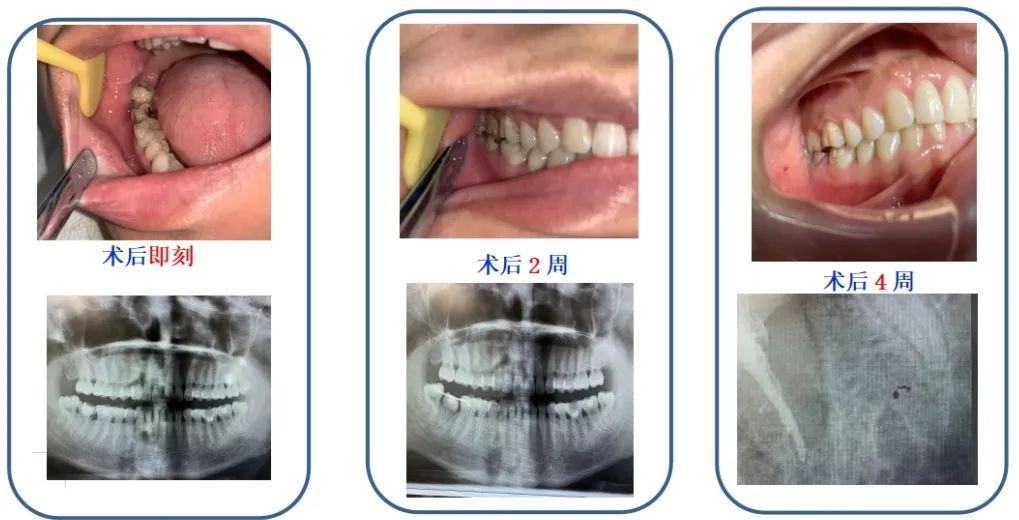

“前段时间牙齿一咬东西就痛,现在已经能正常吃饭了,用的还是自己的牙齿呢!现在的社区真是太厉害了,这么高难度的治疗也能做,真是方便了我们周围居民。” 范女士一周前吃坚果时不慎将牙齿咬裂,抱着试试看的心情来到西渡街道社区卫生服务中心口腔门诊,该中心口腔科李医生在检查后确定了诊断,给范女士预约了下沉坐诊的市九院口腔科专家。经过专家的诊察也明确这个牙齿已无法保留了,提供给了范女士两种方案,其一种牙,其二智齿移植。经过充分解释和沟通,范女士选择了智齿移植方案,她也想让自己的智齿能够“废物”利用。治疗一个月后复诊,移植后的牙齿恢复得非常好。 口腔健康是健康生活的重要组成部分,是维持和享受生命,提高生活质量的基石。随着生活水平的提高,人们对口腔健康的关注度也越来越高。西渡街道社区卫生服务中心已成功创建标准化口腔诊室,持续提升口腔诊疗水平,方便社区百姓。 温馨的就诊环境 独立服务功能区域:候诊区、诊疗区、消毒供应室、放射检查区、健康宣教区、模型间。 齐全的诊疗设备 专业的服务团队 口腔科服务内容:诊疗服务项目:龋齿充填、根管治疗、牙周基础治疗、各类牙齿拔除、牙体缺损修复、活动修复、固定修复以及儿童口腔保健等服务。 口腔科服务时间:周一到周六全天上午8:00~11:00 ,下午13:00~16:00 门诊地址:西渡街道扶港路209号 咨询电话:021-37130209(温馨提示:口腔科就诊需要中心服务号预约哦!) 口腔专家团队 周卓军 主治医师 上海市第九人民医院 擅长:复杂根管治疗、阻生牙拔除、种植修复、青少年牙齿正畸。 专病时间:每周四 门诊地点:西渡街道扶港路209号 沈军 主治医师 上海市奉贤区牙病防治所 擅长:常见牙体牙周病的治疗、牙列缺损的修复、种植治疗。 专病时间:每周五上午 门诊地点:西渡街道扶港路209号 李伟 主治医师 西渡街道社区卫生服务中心 擅长:各类固定修复、活动修复治疗、复杂牙齿拔除。 李子轩 医师 西渡街道社区卫生服务中心 擅长:各类牙体缺损修复治疗、前后牙根管治疗、复杂牙齿拔除。 就诊预约流程 第一步:扫码【西渡街道社区卫生服务中心服务号】并关注 第二步:点击医疗服务选择门诊专病预约 第三步:填写信息完成注册并进行预约 第四步:选择口腔科门诊与就诊时间 第五步:完善相关信息并确认预约 地址:西渡街道扶港路209号 咨询电话:37130209 咨询时间:周一至周日上午8:00~11:30;下午13:00~16:00